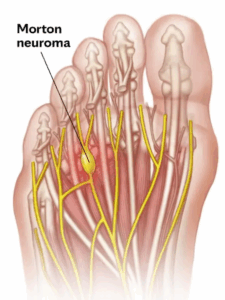

Plantar neuroma

Morton neuroma is a damaged, enlarged nerve that causes pain on the bottom of the forefoot, usually in the area behind the third and fourth toes. The pain is usually sharp or burning. There may be pain, tingling or numbness spreading into these toes.